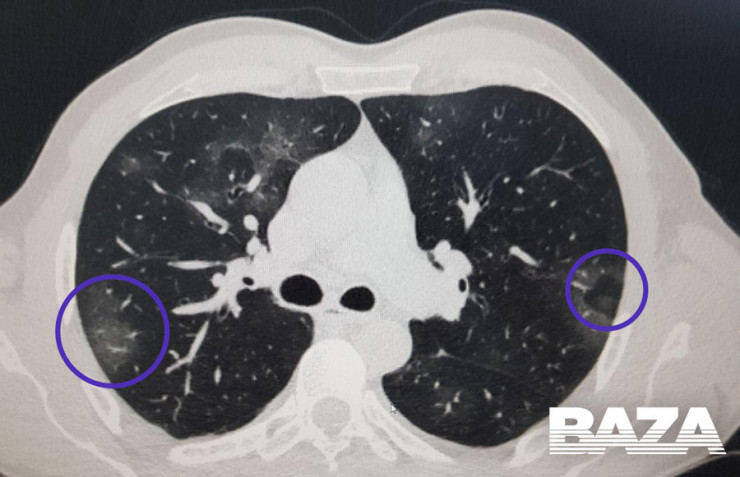

На ранней стадии развития вирусной пневмонии (проявляется до четвертого дня заболевания) "матовое стекло" возникает не более чем в трех очагах. При этом уплотнения распространяются преимущественно в нижних долях и по периферии, а их максимальный диаметр не превышает три сантиметра. Из-за повреждений в альвеолах скапливается жидкость, которая приводит к нарушению кислородного обмена и кислородному голоданию пациента, такие пациенты начинают жаловаться на одышку и затрудненность дыхания.

Затем пневмония начинает прогрессировать. В течение пяти-восьми дней количество уплотнений по типу "матового стекла" становится больше, и они постепенно трансформируются в очаги консолидации по периферии легких.